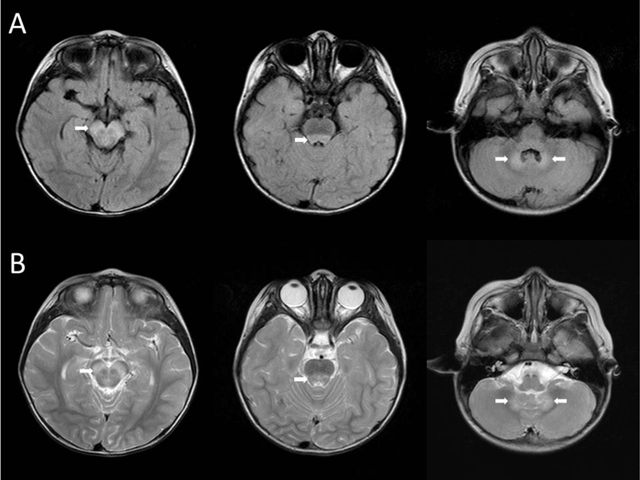

Figure 1

FLAIR (A) and T2WI (B) demonstrate hyperintense lesions in the midbrain, dorsal pons, and cerebellar dentate nuclei (white arrows).